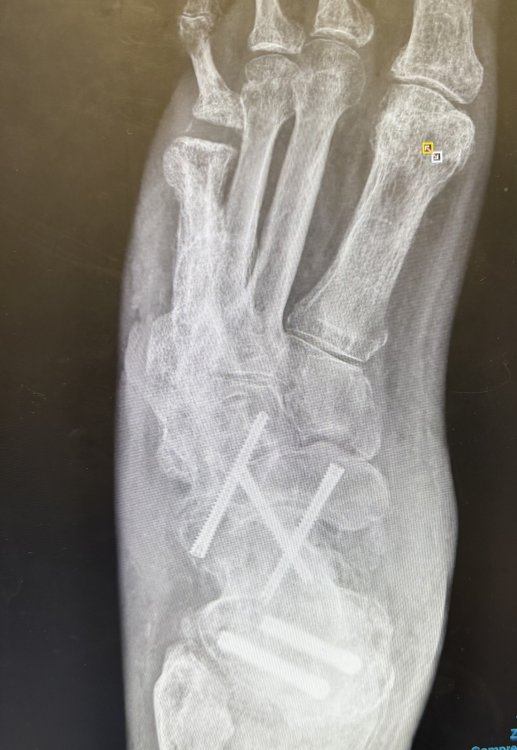

Ashley D Austin Posted October 3 Posted October 3 (edited) I have had foot surgery and the bone in my foot is now permanently higher than it was before and it is very painful to wear any type of closed leather shoe or boot. Soft hiking boots and sneakers are much more comfortable. This spring, I attended a state match and was told I had to wear "cowboy boots". I looked around and saw men wearing leather and soft lace-up shooting boots (which are not cowboy boots), lace-up soft hiking boots, sneakers (tennis shoes), and one that was wearing black socks and black sandals. I am not complaining about being singled out, but I would like a definitive answer from SASS about what the official determination is on footwear for age-based categories? Edited October 3 by Ashley D Austin 2 Quote